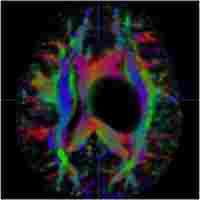

| Abstract | Stroke is the fourth leading cause of death and the leading cause of long-term disability in USA. Brain imaging data from experimental stroke models and stroke patients have shown that there is often a gradual progression of potentially reversible ischemic injury toward infarction. Reestablishing tissue perfusion and/or treating with neuroprotective drugs in a timely fashion are expected to salvage some ischemic tissues. Diffusion-weighted imaging based on magnetic resonance imaging (MRI) in which contrast is based on water motion can detect ischemic injury within minutes after onsets, whereas computed tomography and other imaging modalities fail to detect stroke injury for at least a few hours. Along with quantitative perfusion imaging, the perfusion–diffusion mismatch which approximates the ischemic penumbra could be imaged noninvasively. This review describes recent progresses in the development and application of multimodal MRI and image analysis techniques to study ischemic tissue at risk in experimental stroke in rats. |

| Subject Keyword | MRI Perfusion–diffusion mismatch ADC CBF DWI PWI Experimental stroke model Rodents Oxygen challenge Predictive mode Magnetic resonance imaging Rats Hyperperfusion fMRI Vascular Surgery Neurosurgery Neurosciences Cardiology Neurology |